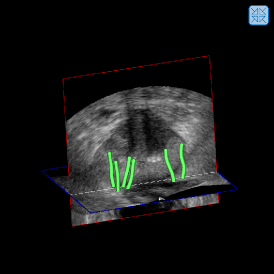

The first experiment evaluates the capacity of the kinematic probe movement model to estimate a probe position sufficiently close to its real position with respect to the gland. For this test, 786 registrations of the biopsy volumes of 47 patients were performed with the corresponding panorama volumes. The registrations were then visually validated either by the clinician immediately after biopsy acquisition or off-line by one of the authors. This was carried out using a volume viewer that allows to overlay and to explore the reference and the tracking volume after application of the registration transformation (see Fig. 13). Note that the accuracy of a large and randomly chosen subset of the registrations classified as valid was evaluated to 0.8±plus-or-minus\pm0.5 mm, cf. the accuracy study presented in Sec. 6.2, which indicates that only few registrations were falsely identified as correct. In this study, 769 (97.8%percent\%) volumes were classified as valid, and 17 (2.2%percent\%) were classified as failures. The 17 failures occurred with volumes that did not contain enough information about the prostate, i.e. the tracked object was literally ”out of view”. This was caused by inadequate US depth or probe pressure (prostate capsule not visible) in 11 cases, partial probe contact with the rectum in 1 case, extremely lateral volumes containing only a small part of the prostate in 4 cases and an incomplete panorama in 1 case. Note that the failures were not caused by patient movements.

Refer to caption

Figure 13: Viewer for visual validation. The viewer shows transverse (a), sagittal (b) and coronal cuts (c) simultaneously. The registration volumes are overlaid: the upper-left and lower-right corners of each view show the tracking volume, while the lower-left and upper-right corners show the reference volume. The green cut point is the 3D point where the three image planes intersect. The user can move the cut point freely in each view, allowing him to explore the entire volume (changing the point in one view changes the spatial position of the other two views).